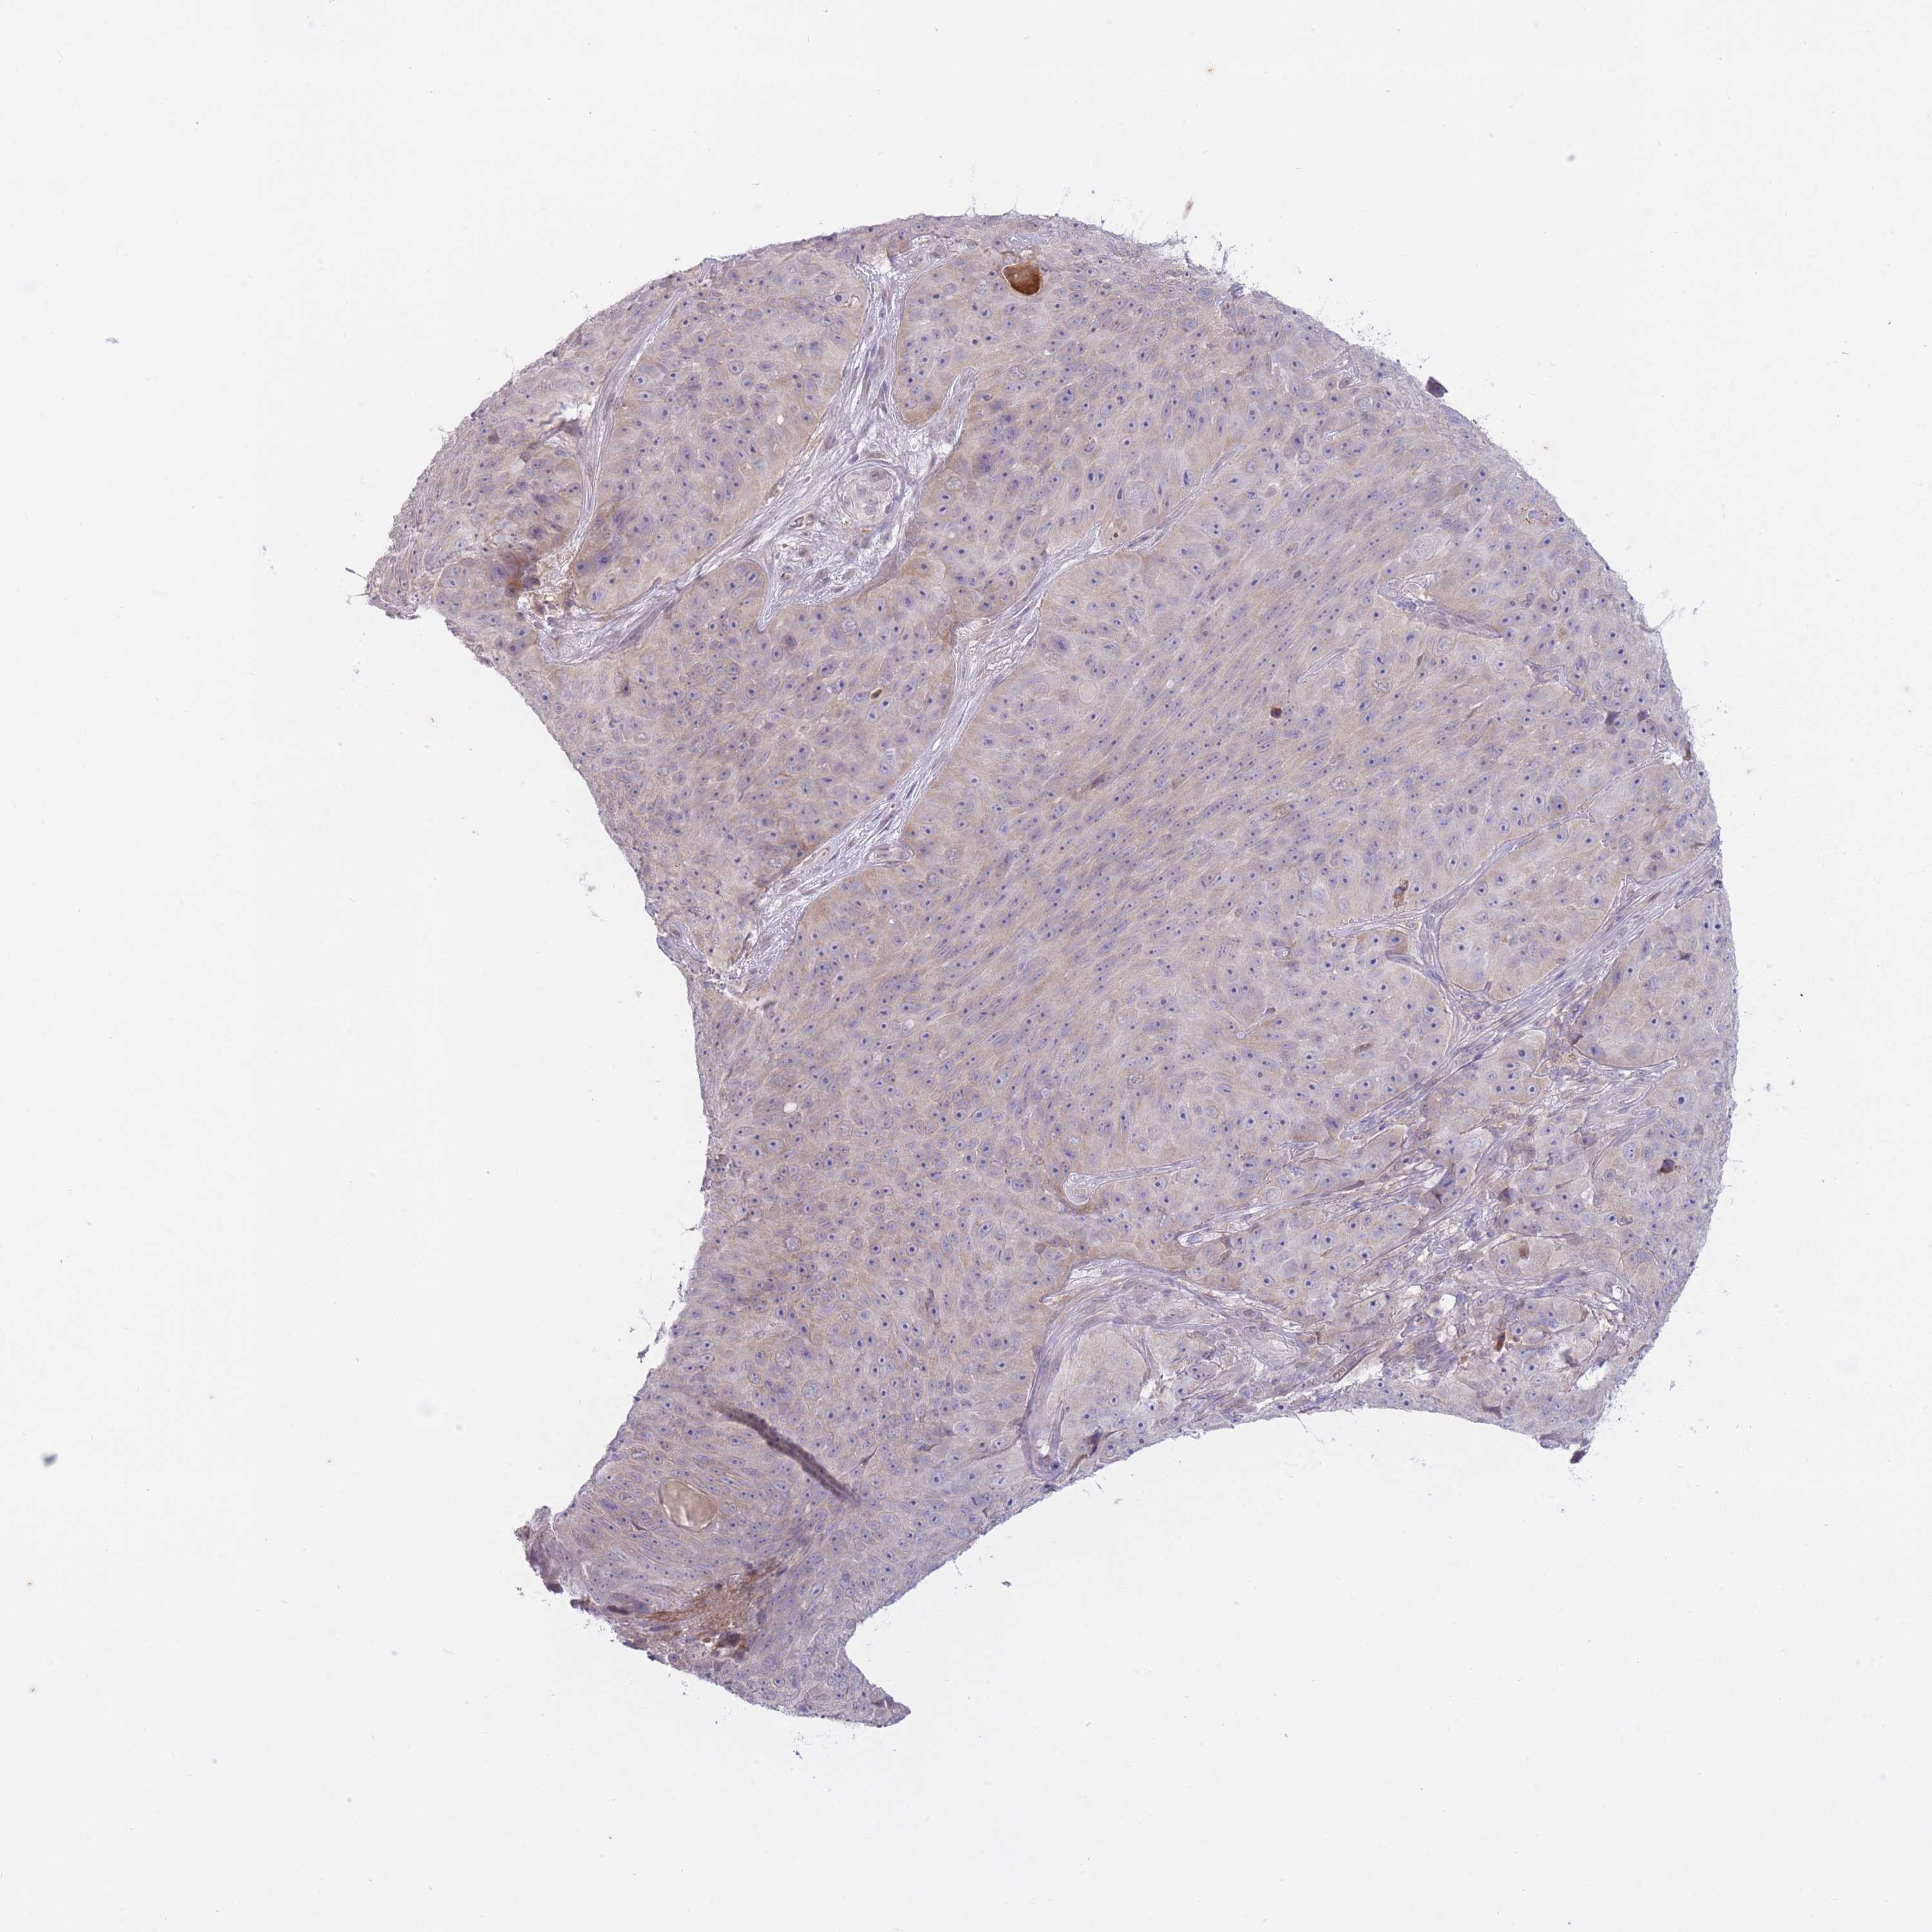

SKIN CANCER - Protein expressioni

A mouse-over function shows sample information and annotation data. Click on an image to view it in a full screen mode. Samples can be filtered based on level of antibody staining by selecting one or several of the following categories: high, medium, low and not detected. The assay and annotation is described here.

Antibody stainingi

Antibody staining in the annotated cell types in the current human tissue is reported as not detected, low, medium, or high, based on conventional immunohistochemistry profiling in selected tissues. This score is based on the combination of the staining intensity and fraction of stained cells.

Each image is clickable and will lead to virtual microscopy that enables deeper exploration of all samples and also displays staining intensity scores, fraction scores and subcellular localization as well as patient and tissue information for each sample.

Antibody HPA052278

Squamous cell carcinoma, metastatic, NOS